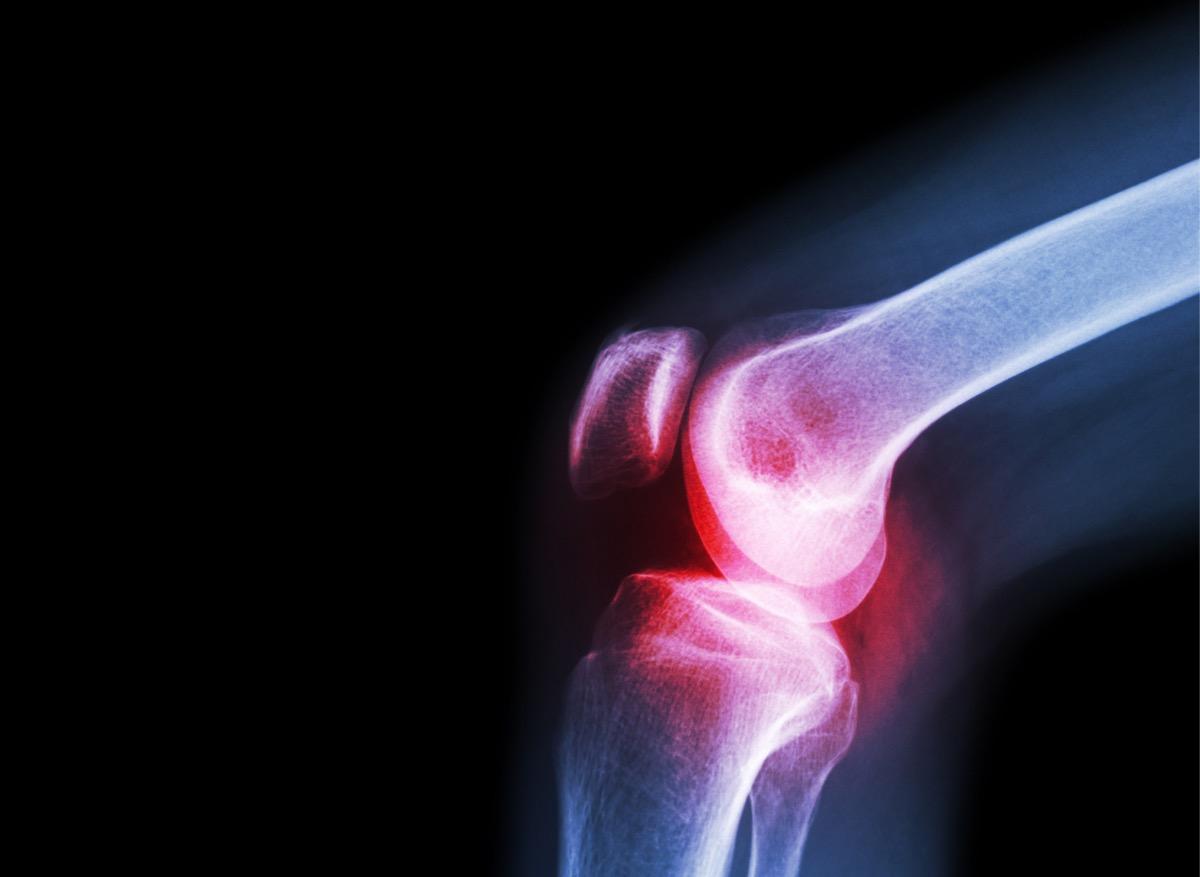

- Un hydrogel pour remplacer le cartilage dans l'arthrose du genou a été mis au point aux Etats-Unis

La science est parfois capable de mimer la nature à la perfection ! Aux États-Unis, des chercheurs ont mis au point un hydrogel dont les caractéristiques sont similaires au cartilage présent dans le genou : il a la même force et la même élasticité. Cette découverte, dont les détails sont publiés dans la revue Advanced Functional Materials, pourrait permettre d’éviter la pose d’une prothèse chez les patients souffrant d’arthrose sévère.

Le cartilage est une partie primordiale des articulations, il les protège en amortissant les chocs. Mais au fil des années, il peut s'user, voire disparaître. Chez les personnes atteintes d'arthrose, il se dégrade progressivement. Sa consistance est particulière car il est à la fois solide, ce qui lui permet de supporter le poids du corps, et en même temps souple, pour amortir. Depuis les années 1970, des scientifiques cherchent à développer un hydrogel pour remplacer le cartilage, mais la matière n’était jamais suffisamment solide ou souple, ou s’usait trop rapidement.